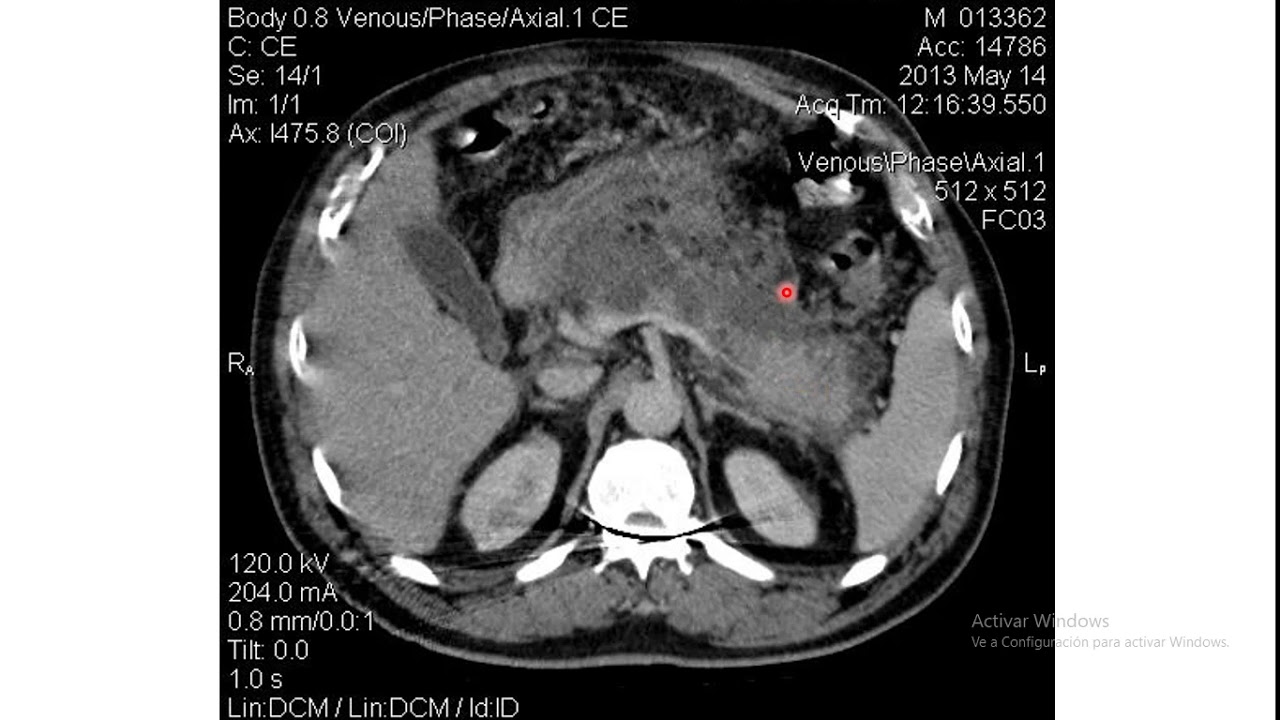

agrandamiento difuso del páncreas que se va a ver así bien Ahora si tenemos una clasificación c significa que existen anomalías intrínsecas del páncreas asociados a cambios del tejido peripancreática la palabra clave aquí es peripancreática lesión O daño a nivel peripancreática que justamente significa alrededor o en los bordes directamente del páncreas que llegaría a ser esto que estamos viendo acá miren esa lesión a nivel del páncreas que justamente se refleja de esta forma bien Ahora pasamos en la clasificación al a la clasificación D que justamente es la presencia de una colección mal definida principalmente de líquido

como estamos viendo acá miren aquí tenemos al páncreas y acá tenemos incluso está un po poco aumentado de tamaño ya que tenemos a la colección de líquido mal definida que justamente se vería de esta forma bien y finalmente tenemos a la categoría E que es la presencia de dos o más colecciones líquidas mal definidas o una colección de gas acá tenemos entonces varias colecciones líquidas que se encuentran mal definidas o directamente una colección de gas que justamente ya nos indicaría presencia de algún agente infeccioso justamente en esa región y obviamente la clasificación va a ser

dándonos cuenta poco a poco Cómo va avanzando y evolucionando bien entonces a partir de eso ya podemos sacar conclusiones La respuesta es no porque a partir de esta tomografía axial computarizada que dijimos sin contraste ya tenemos una una puntuación pequeña pero debemos eh debemos igualarla o sumarle y adherir justamente otra puntuación que va a ser justamente a partir de una tomografía que esta sí va a ser con contraste que va a determinar los grados de necrosis en el paciente bien entonces los grados de necrosis también nos van a dar diferentes puntos y nos van a

indicar grados de necrosis primeramente tenemos de 0 2 4 hasta seis puntos si tenemos cero puntos Qué significa como acá lo mismo que justamente el páncreas se encuentra normal por lo tanto el porcentaje de necrosis es del 0% si tenemos dos puntos significa que el porcentaje de necrosis se encuentra menor del 30% y cómo se va a ver en la tomografía con contraste se va a ver de esta forma miren acá tenemos la tomografía con contraste y acá tenemos al páncreas Dónde está la necrosis se encuentra justamente acá donde están las flechas miren Acá está

una pequeña cantidad de necrosis que no es el 30% debe ser un 15% o hasta un 18 por pero es bastante pequeña en comparación al páncreas bien entonces solamente dos puntos Ahora cuando tenemos cuatro puntos cuando la necr se encuentra entre el 30 al 50% Y cómo es que se va a ver en la tomografía con contraste muy importante se va a ver de esta forma miren acá tenemos al páncreas que se encuentra hasta acá y todo esto que estamos viendo acá es directamente necrosis por lo tanto ya es del 30 al 50% incluso ya